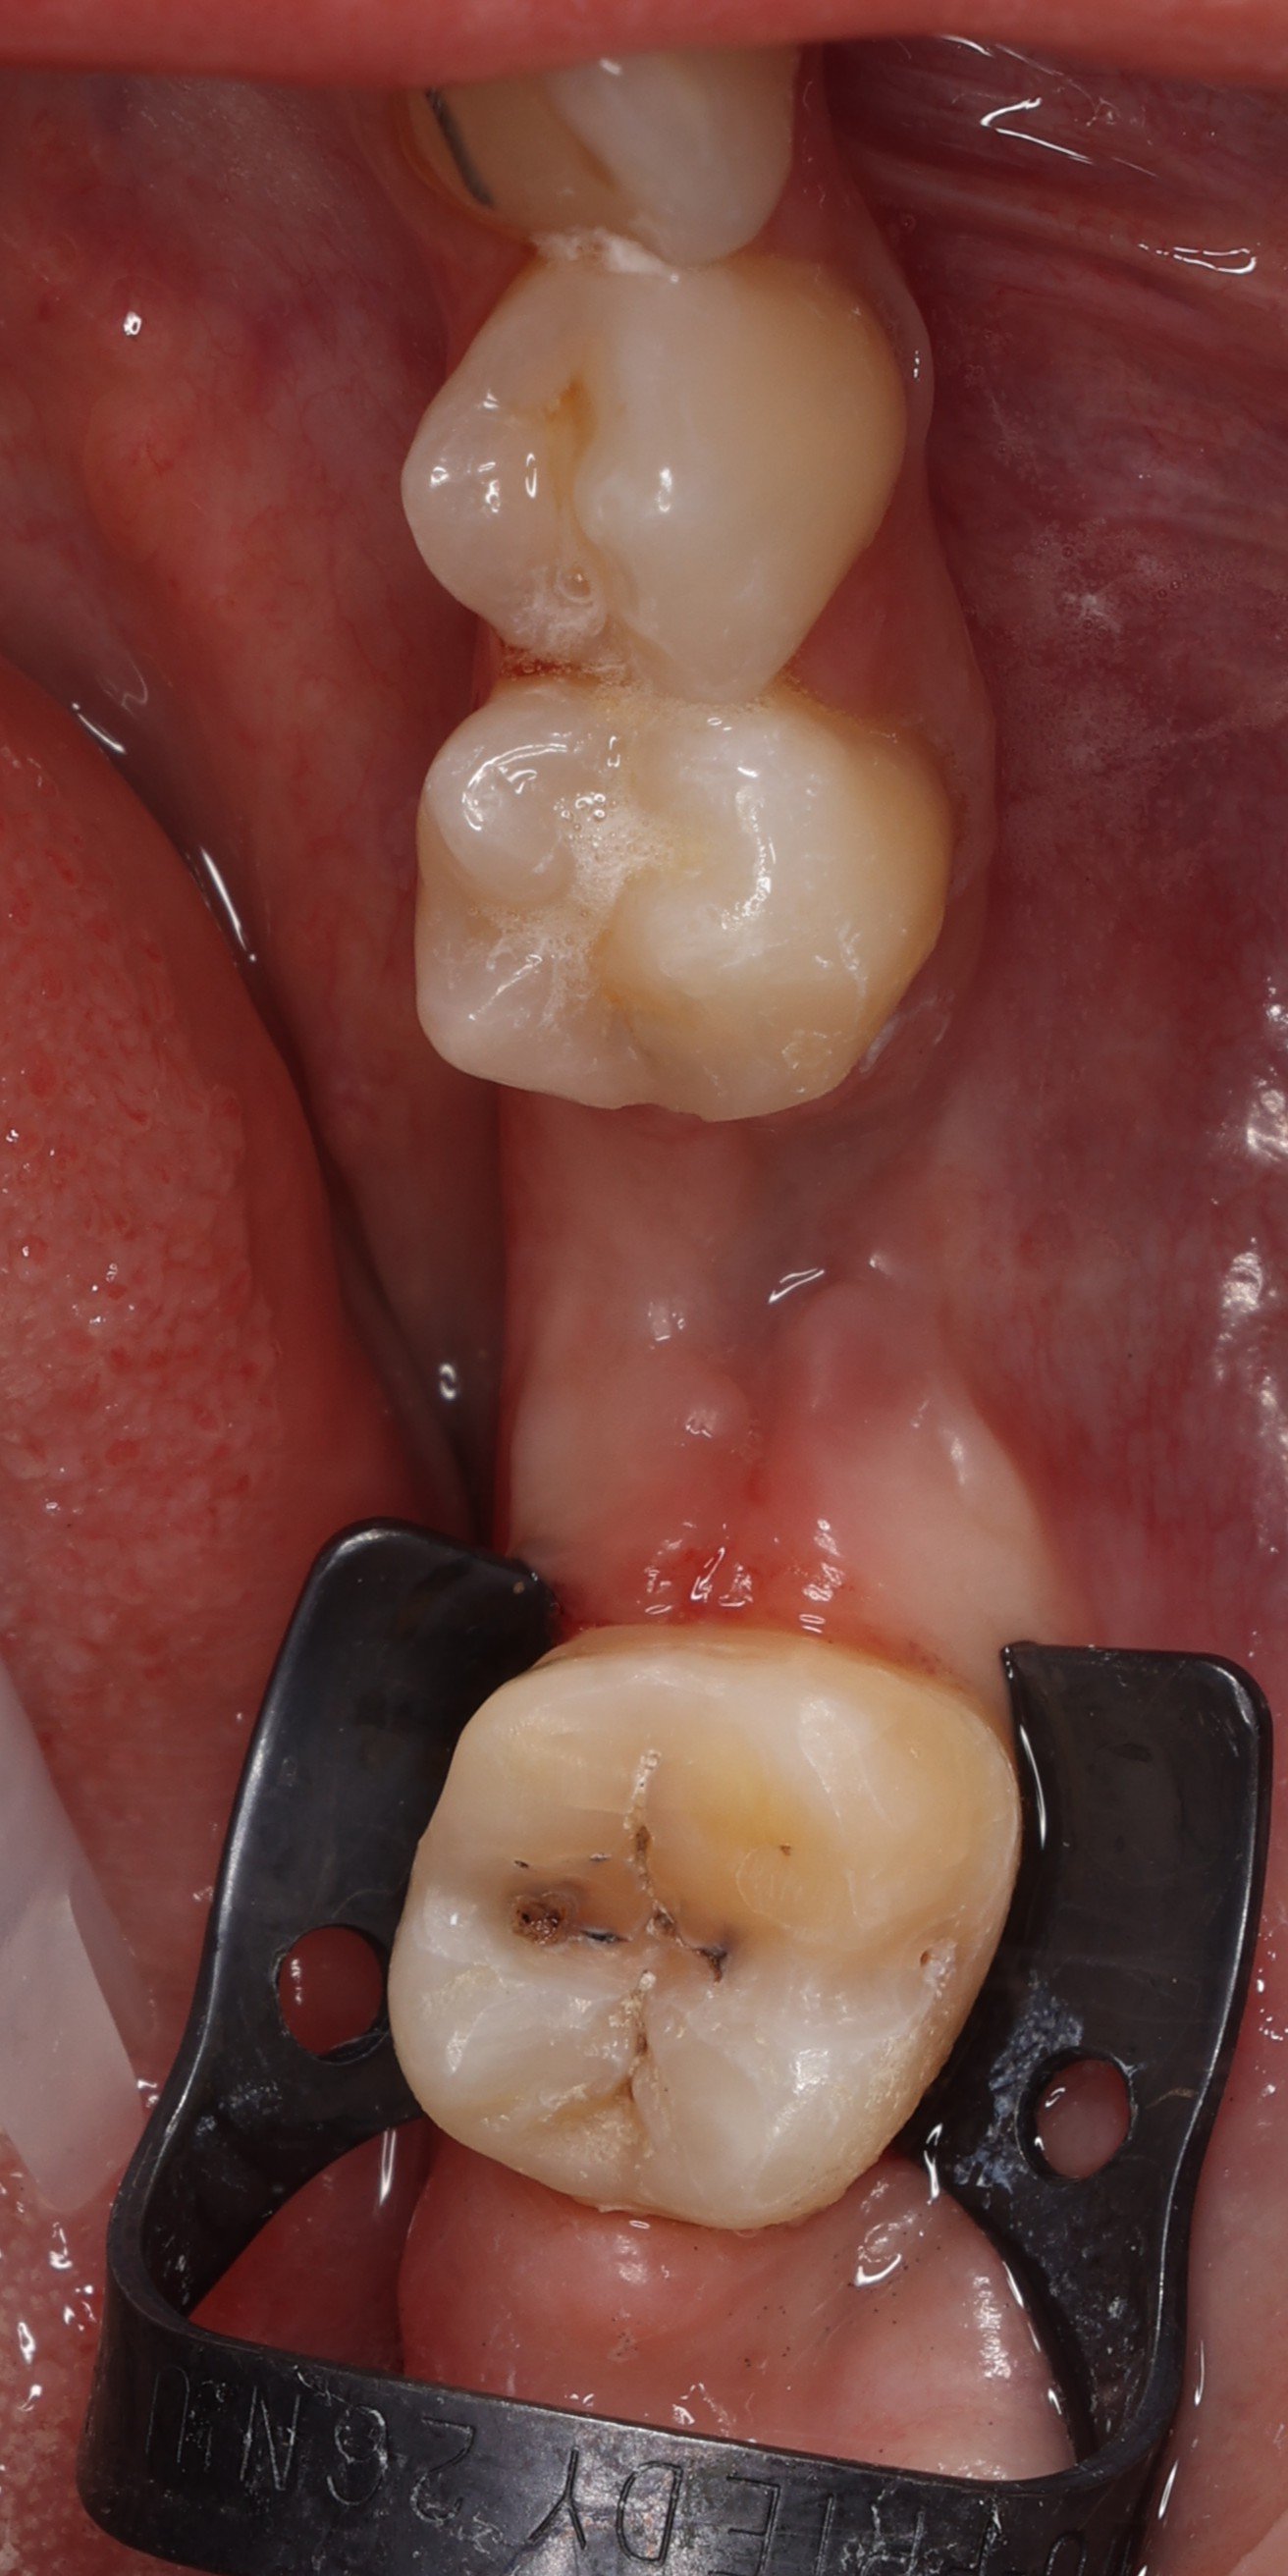

Relativement récents, les bridges collés cantilever postérieurs constituent une alternative fixe, fiable et véritablement minimalement invasive aux implants dans les secteurs postérieurs. Cette thérapeutique qui repose sur des indications bien précises est parfois débattue avec passion sur les réseaux sociaux ou dans les congrès scientifiques. Cependant des études cliniques existent, tout comme des recommandations validées dans des journaux internationaux. Leur succès repose sur des préparations et des principes biomécaniques rigoureux, pourtant simples à intégrer au quotidien. Cette intervention propose un guide clair et opérationnel incluant indications, étapes clés, protocoles d’adhésion et réglages occlusaux pour les mettre en œuvre avec confiance et reproductibilité.